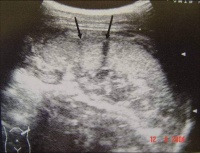

②B型超声检查:

Bk8b4.jpg

脾被摸下破裂

脾真性破裂

B超(左起图1脾中央破裂图2脾被摸下破裂图3脾真性破裂右图胃肠破裂穿孔)检查具有经济方便、可在床边检查、可重复进行动态观察、无创无痛、以及诊断准确率高等优点,因此其在腹部损伤的诊断中倍受重视.应用越来越广泛。 对肝、脾、肾等实质性脏器损伤,B超检查的确诊率达90%左右。可发现直径1— 2cm的实质

血肿,并可发现脏器包膜连续性中断和实质破裂等情况。超声检查对腹腔积液发现率很高。并可根据B超检查估计出腹腔积液的量,即每lcm液平段,腹腔积液约有500ml。由于气体对超声的反射强烈,其在声像图上表现为亮区。因此,B超检查也可发现腹腔内的积气,有助于空腔脏器破裂或穿孔的诊断。

急性胃穿孔。左叶肝前方见气体强回声